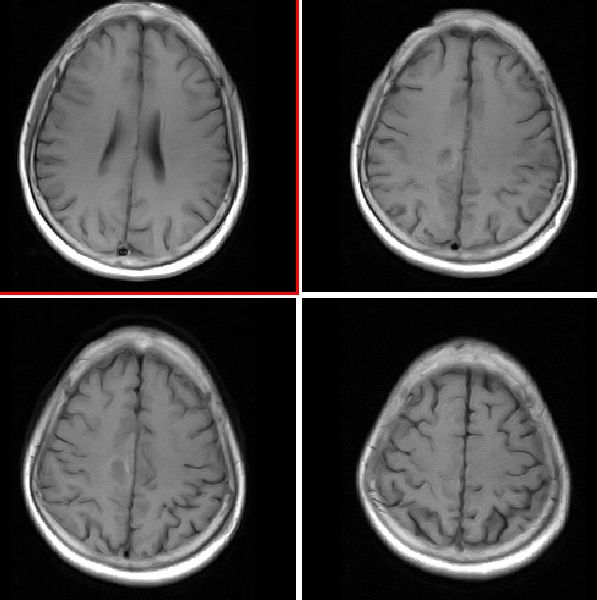

ct

ct表现:右侧中央旁小叶区团状混杂密度病灶,周边不完整环状钙化,病灶周围脑组织无水肿。